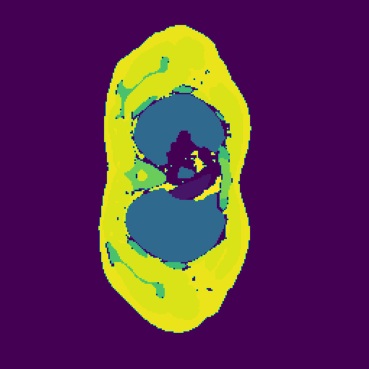

The hypothesis of this experiment is that if the synthetic images generated by our model resemble real medical images in distribution, a segmentation network trained on real data should yield similar performance on synthetic data. By comparing the segmentation results across real and synthetic images, we can quantitatively assess the structural fidelity and semantic consistency of the generated data. The results confirm that segmentation performance on synthetic images is highly comparable to that on real images, indicating that our model successfully captures anatomically relevant structures. This suggests that synthetic data are not only realistic but also potentially beneficial as an augmentation strategy to improve segmentation tasks. Visualizations of the segmentation output are presented in Figure 6.

The goal of our research is not to generate fancy or visually appealing images, but rather to produce images that are useful for downstream tasks. Our focus is on creating synthetic data that have small domain gap with real data, helping to address the bottleneck of data scarcity in the field of machine learning for medical imaging. By generating images that are meaningful for specific tasks, we aim to improve the performance of models in clinical applications, ultimately driving advancements in medical image analysis where labeled data are often limited. In this experiment, We first train a 3D segmentation network using the images and the corresponding semantic maps from training set of the real Duke Breast dataset. The model and training details can be found in the Appendix B. The purpose is to allow the network to learn how to segment anatomical structures from real MRT data. After completing the training phase, we evaluated the segmentation network on four different datasets as shown in Table 2: (1) real images from the Duke Breast dataset training set, (2) real images from the Duke Breast dataset test set, (3) synthetic images generated by our SegGuidedDiff model [26] using semantic maps from the Duke Breast test set, and (4) synthetic images produced by our Med-LSDM model based on the same semantic maps. By evaluating the segmentation results on different real and synthetic images, we aim to investigate the effectiveness of the generative model in producing realistic images that could yield similar segmentation results to real data, suggesting that real and synthetic images lie in similar regions of the data distribution.

Table 2 presents the segmentation performance, measured by the Dice similarity coefficient averaged over all semantic classes, across different data sources. The real training data achieve the highest Dice score of 0.750, which indicates that the segmentation model achieves a 75% overlap between the predicted region and the ground truth. When tested on the real test set, the score falls slightly to 0.715, indicating good generalization.

In contrast, the segmentation result of synthetic data generated by SegGuidedDiff using 2D semantic map slices shows significantly lower performance (Dice = 0.602). Notably, SegGuidedDiff generates images slice-by-slice in 2D without modeling the full 3D spatial context. As a result, the synthesized volumes often suffer from inter-slice inconsistencies and unrealistic spatial structures, which negatively impact the downstream segmentation performance.

Our Med-LSDM-generated data, in contrast, achieves a Dice score of 0.70964, which is much higher than SegGuidedDiff and closely approaches the real data test performance. This indicates that our method’s 3D generation strategy successfully captures anatomical coherence across slices and produces realistic volumetric data. It is also important to note that the synthetic volumes are directly saved in NIfTI format without any post-processing, demonstrating the practical applicability and robustness of our framework.